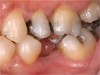

Figure 1  Long-standing missing tooth No. 19.

Figure 1